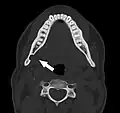

Axial computed tomograph of the same person. The Stafne defect appears as a well corticated 1 cm round defect in the medial cortex of the mandible in the right angle of the jaw (arrowed).